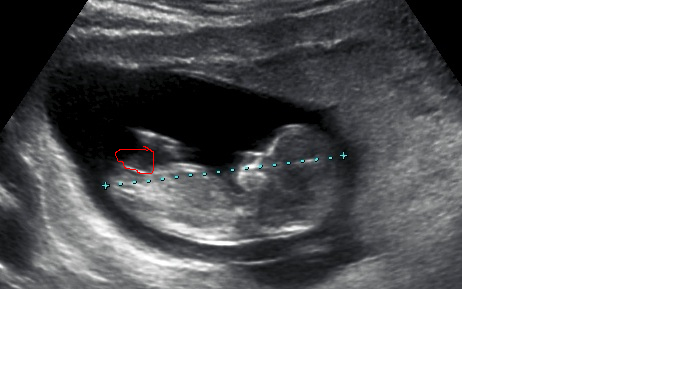

Would love some guesses and predictions on my 11w6d pics (i realise its not in the 12th week, but its only 1 day off!!)